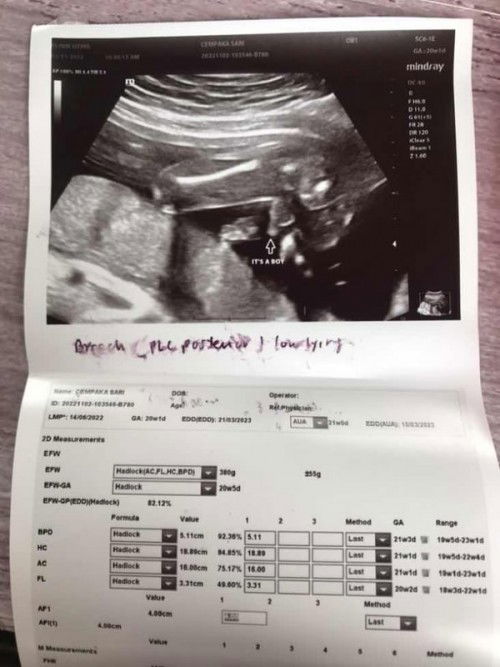

Ada sesiapa yang experience uri dekat bawah pada usia kandungan 20minggu ?, Saya pergi scan gender dan alang2 doctor check sekali kedudukan uri, Doctor kata uri dekat dengan pundi kencing dalam 1.6cm, Normal range sepatutnya 2cm keatas, Doctor just cakap kalau ada bleeding ke apa, terus pergi hospital. Ada pengalaman atau apa2 tips yang saya boleh buat dan elak buat masa sekarang ? Teringin sangat nak bersalin normal, Saya percaya yang baby akan pusing satu hari nanti, dia masih ada masa ❤️. #ingintahu #firstbaby #pleasehelp #pleasehelp #bantusharing